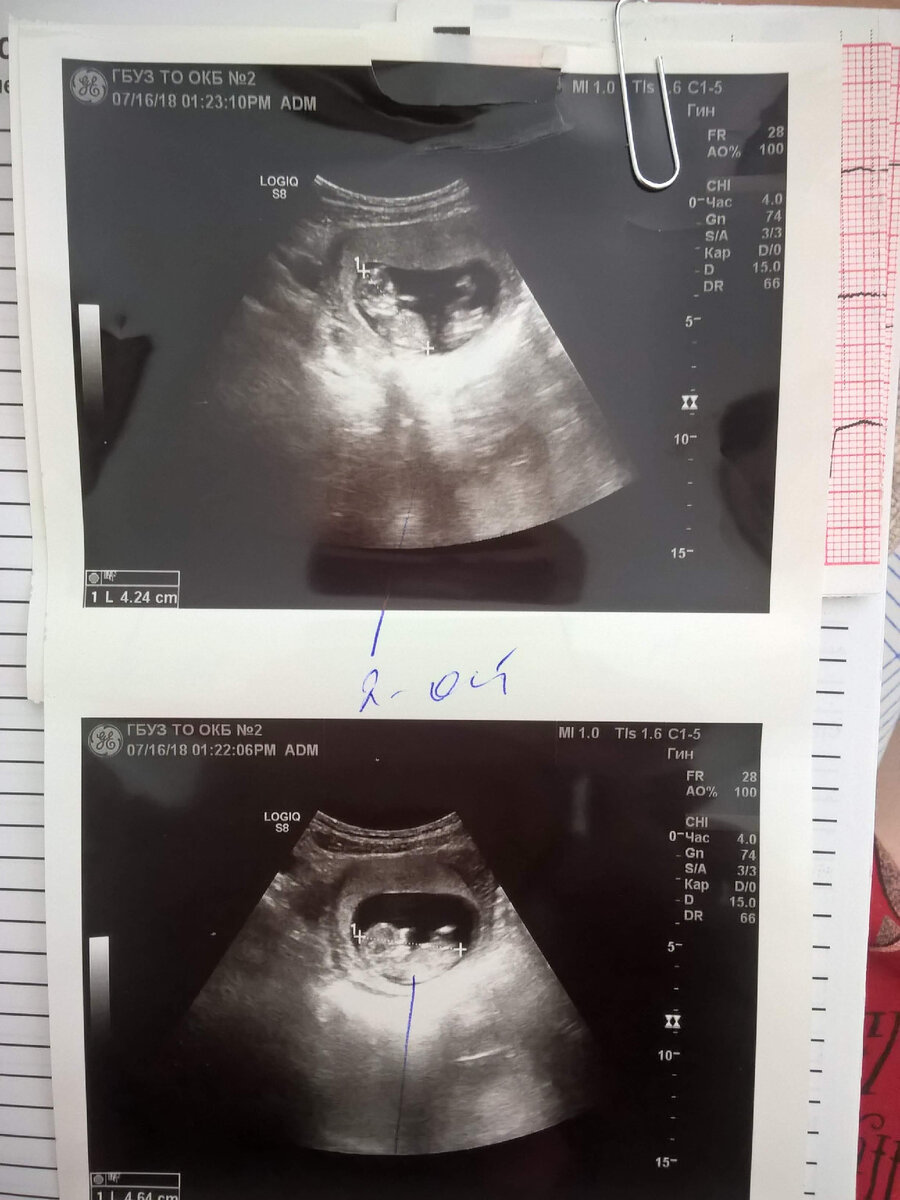

УЗИ с двойней на 11 неделе

Через 2 дня пошла к гинекологу, на учёт встать. Она, как чувствовала, повела меня сразу на УЗИ, чтобы беременность подтвердить. Долго так смотрела и молчала. Я уж решила, что тесты ошиблись. И тут: "Так у вас двойня! Щас у вас есть один ребенок? А будет три"

Вышла в коридор, мужу же надо рассказать... А язык не шевелится все ещё. Сфоткала результат УЗИ с двумя "яичками" и отправила по Вайберу. Тут же звоню - не берет😅 Всё, думаю, сбежал.

В 10 недель я поехала вставать на учёт. Там предупредили, что придется часто сдавать анализы и делать УЗИ, т.к. плоды однояйцевых и есть риск их сращивания. Жуть, конечно!

Старалась беречь себя, но в 11 недель попала в больницу с кровотечением. Положили на сохранение, образовалась внутриматочная гематома(( Около недели провалялась, там же на мониторе увидела впервые своих малышей. Один из них (даже знаю кто) активно махал руками и ногами😍. К счастью, угроза миновала, меня выписали.